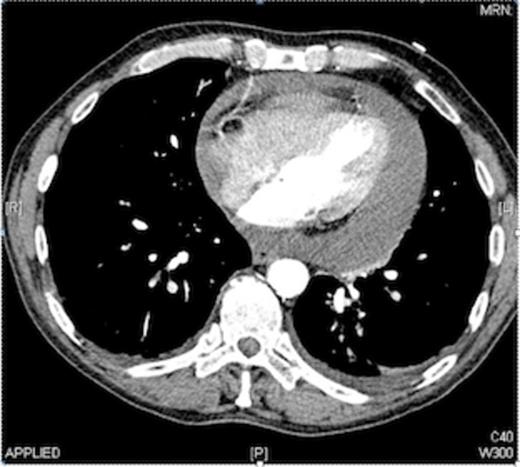

The CT findings were a moderate to severe pericardial effusion, with a fluid rim of approximately 2 cm, around the whole pericardium (as shown in Fig. 1).